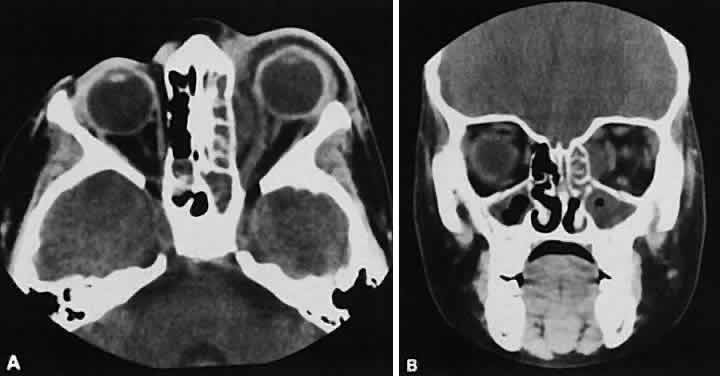

After the orbit has been visualized adequately, it also has been our practice to obtain 10-mm axial slices through the remaining portion of the head to complete the study. Intravenous contrast material usually is given, although the low-density orbital fat produces an inherent high level of contrast for most orbital CT studies. Intravenous administration of iodinated contrast medium is most helpful in detecting intracranial extension of an orbital process or identifying a pathologic process involving the optic nerve/sheath, most notably optic nerve sheath meningioma. Specific contraindications for contrast material include allergy or renal failure.

By altering window setting and level of attenuation on the console, subtle differences in tissuecomposition or bone changes can be appreciated.Window setting refers to the amount of the pixel sampling used by the computer to determine image contrast. Level refers to the scale of density used by the computer to create the image. Both the window setting and level of attenuation are extremely important, for example, when evaluating lesions in the fossa of the lacrimal gland, when the surrounding bone must be examined carefully for either pressure thinning or tumor erosion.

An appreciation for the various pathologic processes that affect the orbit is facilitated by an understanding of the normal orbital anatomy (Fig. 1). The orbit is a pyramid-shaped bony structure bounded inferiorly by the maxillary sinus, medially by the ethmoidal sinus, and superiorly by the frontal sinus. The sphenoidal sinus is situated posteriorly along the medial orbital wall and has a common wall with the optic canal. The lacrimal gland lies within its fossa located in the superior temporal aspect of the orbit and can be seen on both axial and coronal views.

The extraocular muscles (EOMs), with the exception of the inferior oblique, originate from the anulus of Zinn in the orbital apex. The inferior oblique takes its origin from the frontal process of the maxilla and is seen occasionally on CT imaging. The superior oblique, after originating from the anulus, courses along the superior nasal orbital wall just above the medial rectus muscle before passing through the trochlea. The rectus muscles conveniently form a muscle cone, which is sometimes helpful in terms of differential diagnosis. Before thinner axial slices and multiplanar imaging were available, an enlarged inferior rectus muscle often was imaged as an apical mass, especially if dysthy-roid optic neuropathy was present. The importance of imaging from two different planes cannot be overemphasized in this situation.